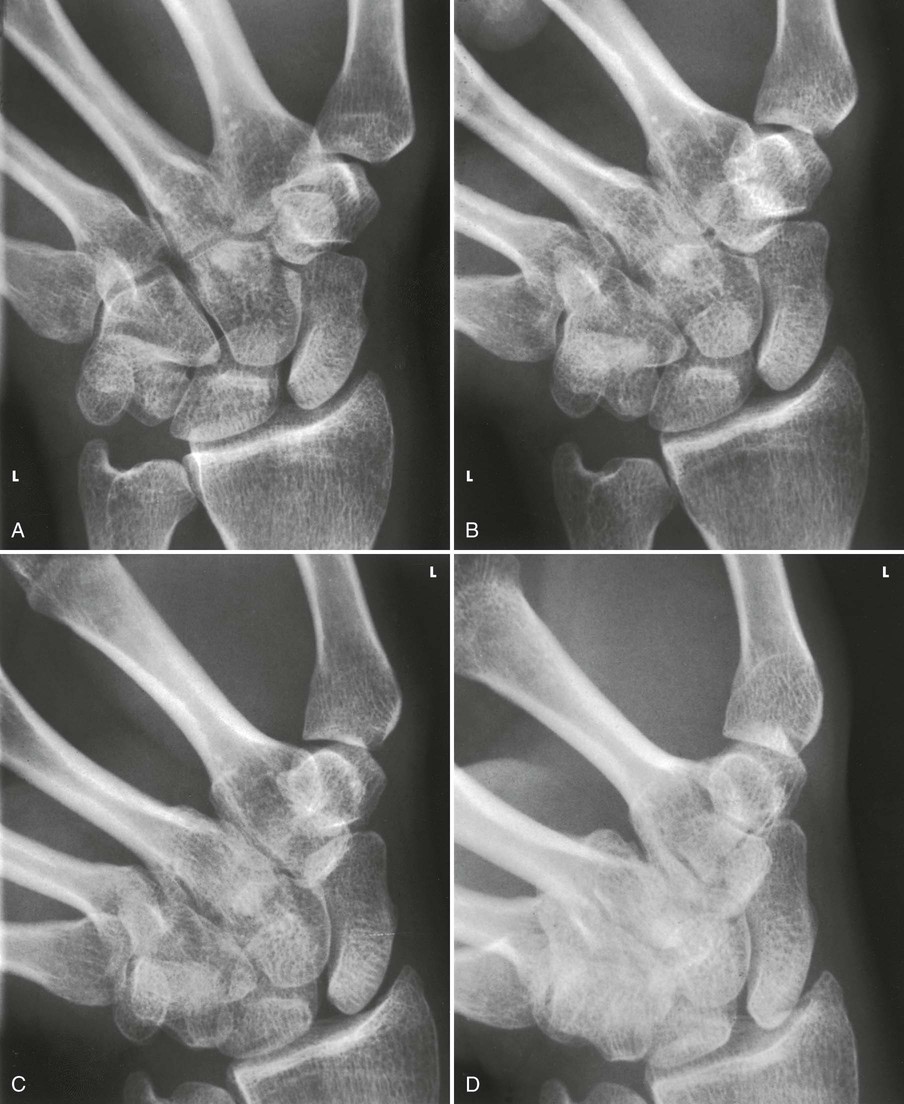

Scaphoid fractures account for 60% of all carpal bone injuries. In 1991, Rafert and Long1 described this method of diagnosing scaphoid fractures using a four-image, multiple-angle central ray series. The series is performed after routine wrist radiographs do not identify a fracture, but symptoms are suspicious for scaphoid fracture.

The scaphoid is shown with minimal superimposition (Fig. 4-92).